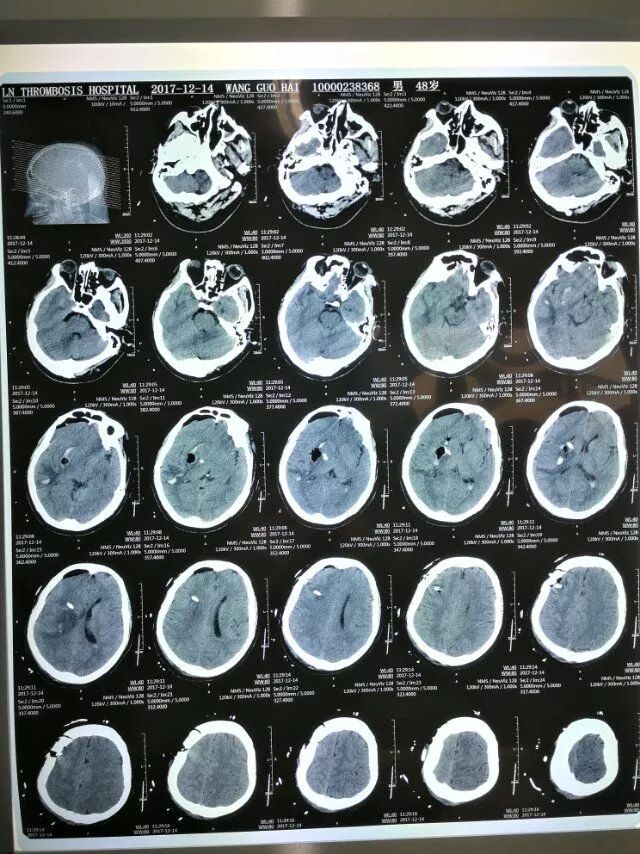

患者男性,53岁,以右侧基底节出血为诊断入院,量约50毫升。

术前片子